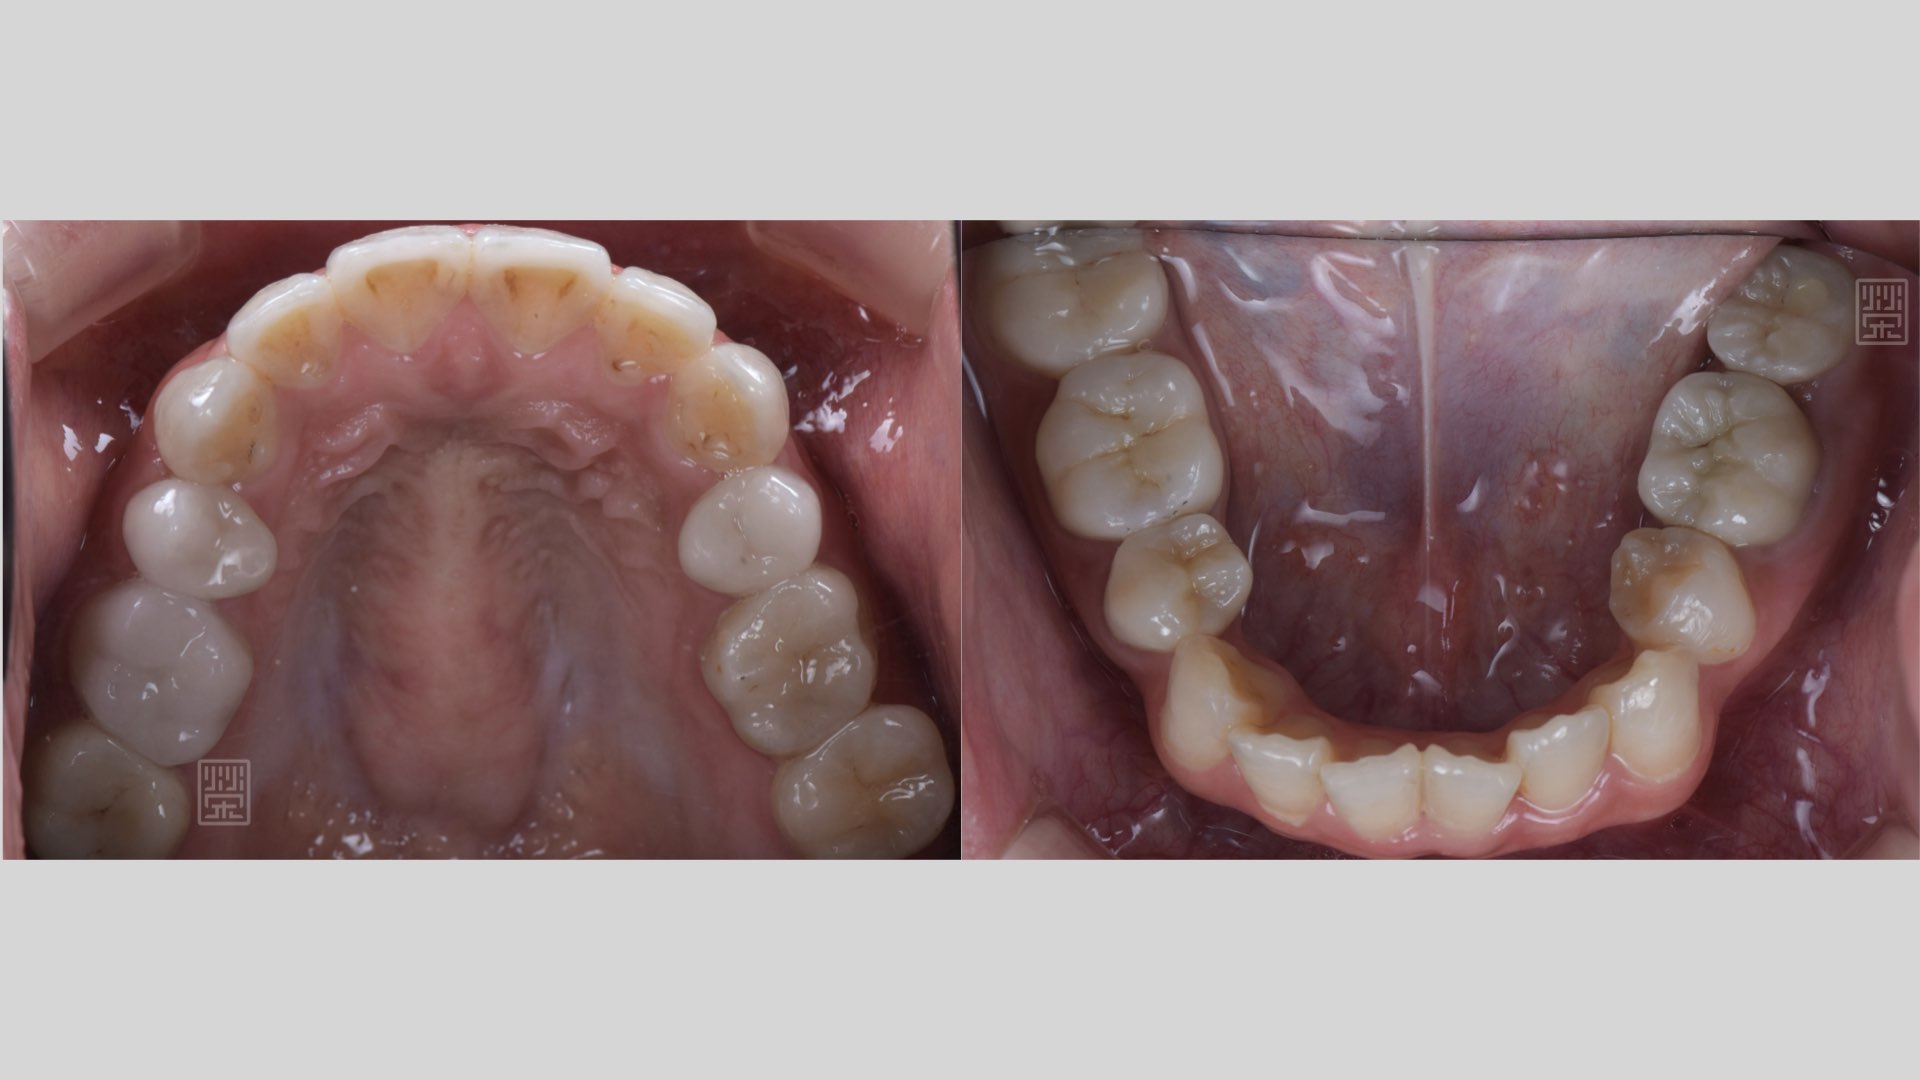

全瓷嵌體完成

重新樹脂填補完畢

重新樹脂填補完畢,門齒比例80%,不宜做牙冠增常術